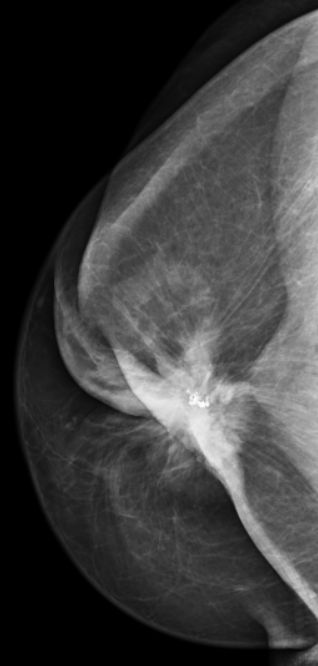

![]() ![]() 73 Jahre alte Frau. Vor 40 Jahren eitrige Mastitis puerperalis links oben außen. Jetzt 50mm großes invasives lobuläres Karzinom links oben außen. Tumor durch Mastitisnarbe maskiert. | ||